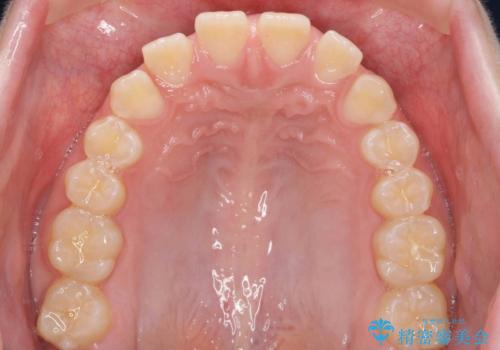

- 前歯の隙間を主訴に来院。

顎の大きさに比べて歯が小さく、隙間が目立っていました。

マウスピース矯正で隙間を閉じる処置を行いました。

隙間を閉じる際、奥歯が倒れたため、途中ワイヤー矯正を併用しています。

上の前歯の隙間を閉じながら前歯を後方に下げているため、口元もひっこみ、口が閉じやすくなりました。